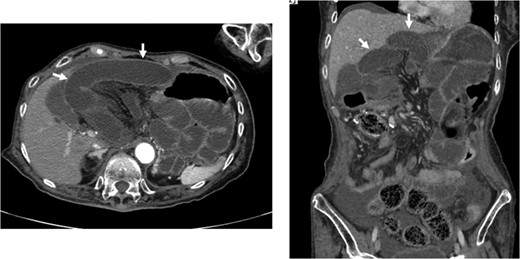

Mesenteric defects are often not closed in laparoscopic colectomy. We herein report a case of an internal hernia projecting through a mesenteric defect following laparoscopy-assisted right hemicolectomy. A 74-year-old woman was hospitalized for the surgical treatment of double colon cancer. Preoperative colonoscopy demonstrated the presence of ascending colon and transverse colon cancers. A laparoscopic-assisted right hemicolectomy was performed. The mesenteric defect resulting from the colectomy was not closed. Three months after the surgery, the patient developed a bowel obstruction. Under a diagnosis of strangulated bowel obstruction, we performed a laparotomy, and found a necrotic small bowel, which had passed into the bursa omentalis through the mesenteric defect. We removed the necrotic small bowel and closed the mesenteric defect by suturing. The patient’s postoperative course was uneventful. An internal hernia projecting through a mesenteric defect following laparoscopy-assisted right hemicolectomy developed a severe strangulated bowel obstruction.

A 74-year-old woman was hospitalized for the surgical treatment of double colon cancer. Her medical history showed that she had been suffering from permanent damage from a cerebral hemorrhage for several years. A colonoscopic examination demonstrated the presence of an ascending colon tumor and a transverse colon tumor. Biopsies performed before surgery revealed that both lesions were well-differentiated adenocarcinomas. A laparoscopic-assisted right hemicolectomy was performed. We divided the sub-middle colic artery and the ileocecal artery that fed the tumors with surgical trunk dissection (D3 lymph node dissection). The right colon moved out through a 5-cm midline incision. The marginal vessels were ligated, and functional end-to-end anastomosis was performed extracorporeally using linear staples. The mesenteric defect resulting from the colectomy was not closed. No herniation of the small bowel through the mesenteric defect was observed laparoscopically. Operation time was 238 min. Blood loss was 10 ml.

Closure of the mesenteric defect caused by anastomosis after colectomy is not performed routinely in laparoscopic surgery [4]. Laparoscopic closure of the mesenteric defect requires a longer operation time, and incomplete closure may produce internal hernia of the small bowel. There is no consensus concerning closure of the defect. Small bowel obstructions related to mesenteric defect are rare in laparoscopic colectomy. In the case reported here, the patient developed a strangulated ileus. A narrow defect caused by mesenteric adhesion may produce the strangulation of the small bowel that passed through the mesenteric defect. The mesenterium of the colon was conglutinated to the pancreas and surgical trunk that were dissected in the first operation, resulting in the formation of a small defect of the mesenterium. Papers reported various types of internal hernias after laparoscopic colectomy [5–9]. In this case, the right hemicolectomy and the lymph nodes dissection in a wide area were necessary because of the double and advanced cancers (pT4a, pN1b, M0, pStage IIIB in ascending colon and pT4a, pN2a, M0, pStage IIIC in transverse colon). This might have allowed the tissues of the mesenterium to conglutinate more easily. Internal hernia after laparoscopic colectomy is rare. However, patients with strangulated bowel obstructions may experience severe illness. An internal hernia projecting through a mesenteric defect following laparoscopy-assisted right hemicolectomy developed a severe strangulated bowel obstruction. Therefore, a closure of the mesenteric defect may be necessary after laparoscopic colectomy.